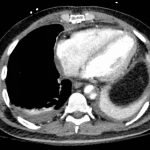

Chest x-ray and CT angiogram was performed to evaluate his thoracic and abdominal vasculature. Chest x-ray did not show any significant widening of the mediastinum. The CT angiogram demonstrated an intimal tear along the aortic arch separating a true and false aortic lumen, consistent with an acute aortic dissection. The true lumen (highlighted in blue in images 1-5) can be identified by continuity with an undissected part of the aorta1. While the false lumen (highlighted in red in images 1-5) can be identified by its crescent shape and larger cross-sectional area.1